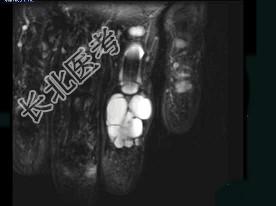

- 单项选择题女,77岁, 发现右手部肿块2周,结合图像, 最可能的诊断是 ( )

A、肌内脓肿

B、多发性腱鞘囊肿

C、骨囊肿

D、血管瘤

E、以上都不是